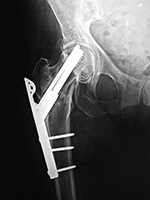

| Left hip cannulated screw fracture |

| 41 year-old man with chronic left femoral neck fracture and fracture of superior cannulated fixation screw. The partially visualized intramedullary nail is for an old femoral shaft fracture. |